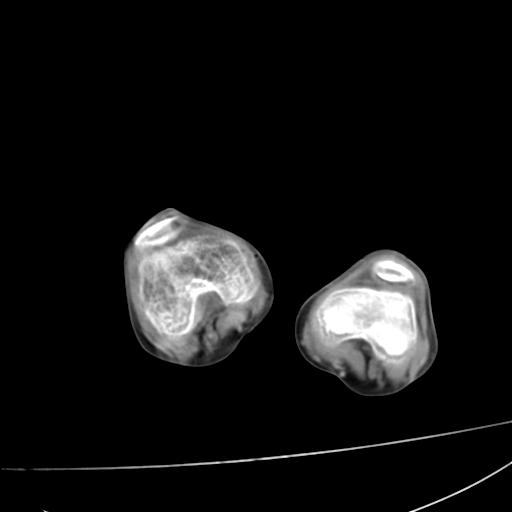

标题: PED0940:M12Y,左股骨下端酸痛畸形 [打印本页]

标题: PED0940:M12Y,左股骨下端酸痛畸形

12岁男孩,左膝关节肿痛8年,近月明显

内生骨软骨瘤?

血友性关节病?